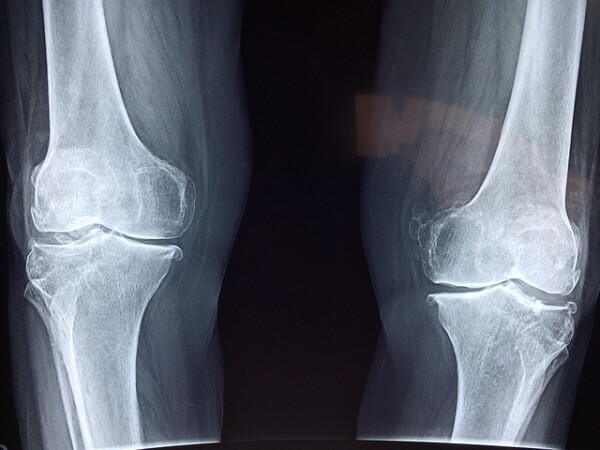

그런데 이런 증상이 40대부터 나타난다면 단순 피로가 아니라 ‘관절 퇴행’의 신호일 수 있습니다.관절은 **연골과 활액(윤활액)**으로 구성되어, 움직임에 부드러움을 주는 중요한 조직입니다.

하지만 노화, 잘못된 자세, 과체중, 운동 부족 등의 원인으로 연골이 점차 닳고, 염증이 발생하거나 통증이 생기면 일상생활에 큰 불편을 주게 됩니다.✔ 참고로, 한국인의 대표 관절 질환:

- 무릎 관절염